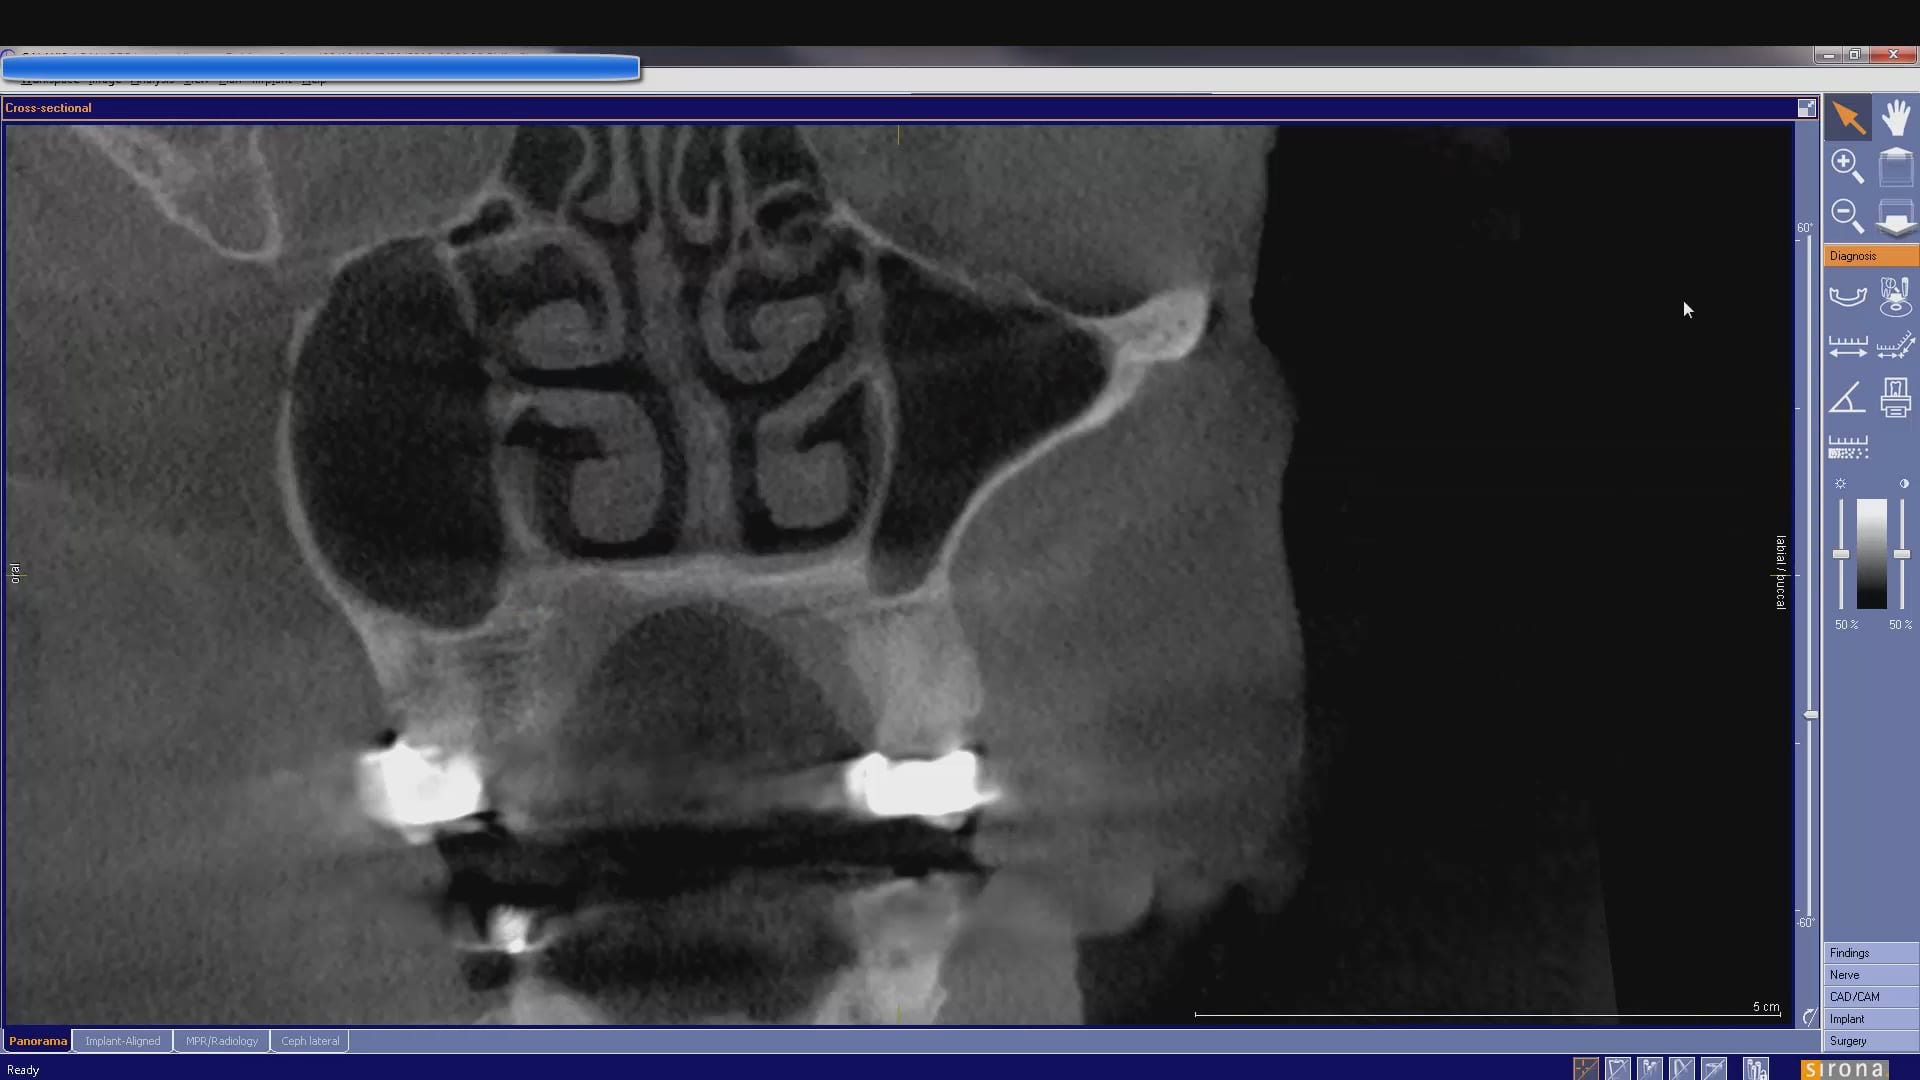

In this case presentation, we utilize the medit i500 to image the pre-existing crown and to fabricate a restoration that is a replica of the pre-existing condition. The patient was advised that the recurrent decay was in close proximity to the canal space and that endodontic treatment may be a possibility. The CBCT showed no evidence of any peri-apical radiolucency and the premolar tested vital prior to treatment